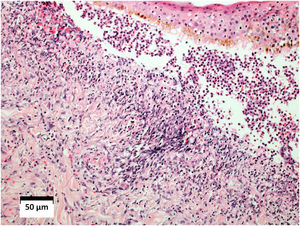

O exame histopatológico da pele revelou vasculite leucocitoclástica, e a imunofluorescência direta foi negativa com anti‐IgM, anti‐IgG e anti‐IgA (fig. 4). A histologia pulmonar evidenciou processo inflamatório granulomatoso com necrose caseosa central. O lavado broncoalveolar revelou três bacilos álcool‐ácido resistentes (BAAR).